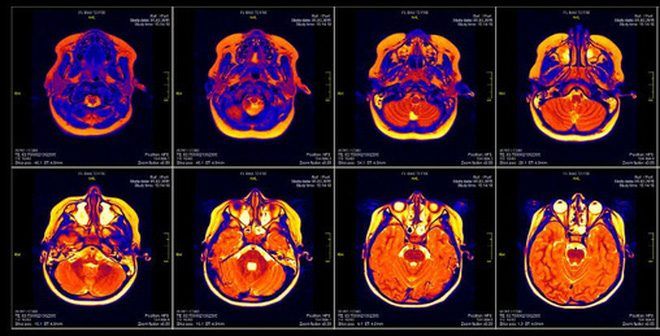

Hình ảnh não bộ qua máy quét cộng hưởng từ MRI.